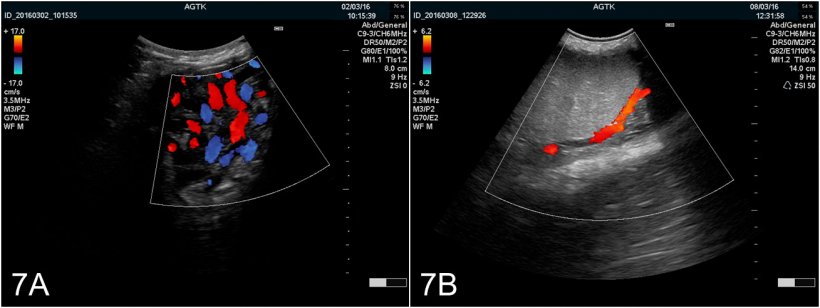

En résumé, l'échographie de l'appareil génital du verrat est une modalité de diagnostic viable qui peut fournir des informations précieuses sur la fonction et la santé du tissu. Même si l'utilisation pratique est actuellement limitée, l'auteur est fermement convaincu que l'utilisation de cette méthode (et d'autres comme le Doppler couleur [Figure 7A et B]) obtiendra une plus grande utilisation chez les vétérinaires porcins comme un outil pour prédire le rendement potentiel des éjaculats et pour diagnostiquer avec précision les problèmes de subfertilité et d'infertilité associée à des tissus malades.

Figure 7: Images du testicule obtenues par échographie Doppler couleur A) Vaisseaux du cordon spermatique B) Artère testiculaire